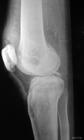

一個hoffa骨折的典型...股骨遠端單髁或雙髁的冠狀面骨折均稱為Hoffa骨折,為關節內骨折。

Hoffa骨折多為高能量損傷,常發生於青壯年。往往伴有膝部其他骨折、半月板損傷、關節軟骨損傷、前交叉韌帶或後交叉韌帶的斷裂以及血管神經的損傷。正位X線片不能對股骨髁冠狀面骨折提供明確診斷,側位片也可能漏診微小的骨折移位。有些X線檢查示移位小,但CT檢查往往示移位大,且有旋轉,這可造成明顯的肢體功能障礙。同時診斷時應考慮膝部後方肌肉及韌帶附著部損傷的可能。骨折線由後上向前下斜形走行,遠端骨折塊易向後上方移位且骨折緣銳利,易損傷動靜脈及脛神經。術中所見常較術前X線片表現複雜。因此對於損傷嚴重考慮伴有嚴重關節面損傷的患者,必要時應作CT或MRI檢查,以明確骨折部位及損傷情況,制定較完善的手術方案。